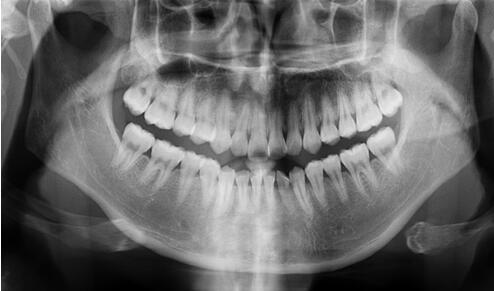

全口曲面断层片

看似复杂,用人话说就是口腔牙齿的X光片。

牙医通过对这张片的分析,能找出潜藏的牙周疾病问题、牙根发育等情况。通常是否拔牙、拔哪个牙、怎么拔,就是靠它了!